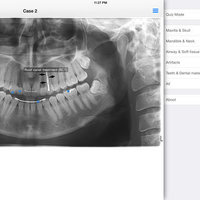

iPanoramic

Panoramic radiographs provide a quick overview of the patient’s teeth, jaws, and bone. This is useful for diagnoses and treatment planning.

The app provides dental students and dental hygiene an easy and fun way to master different anatomical landmarks. Dental practitioners can use the app to refresh their knowledge about panoramic radiographs. The app can be used a quick reference when needed. It's fully interactive and allows knowledge assessment through a quiz mode.